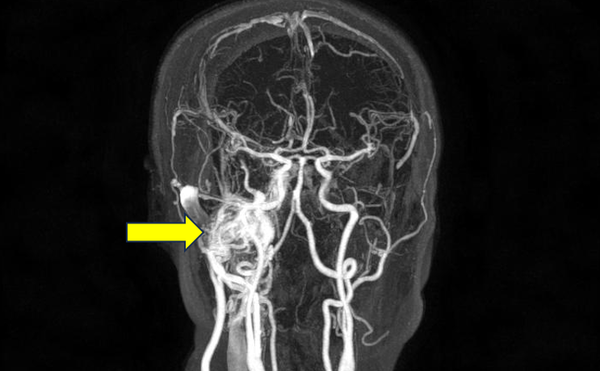

뇌동맥류는 파열되기 전까지는 대부분 증상이 없지만, 간혹 두통을 호소하거나 어지러움을 느끼는 경우도 있다. 자각 증상이 없어서 대부분 건강검진을 통해 우연히 발견된다. 파열되지 않은 뇌동맥류는 CT나 MRI 같은 영상검사를 통해 쉽게 확인할 수 있다. 뇌동맥류가 발견되면 뇌혈관조영술을 통해 치료계획을 세운다.

뇌동맥류 치료는 수술이 유일한 치료로, 수술 방법에 두 가지 종류가 있다. 머리뼈를 열고 뇌동맥류의 입구를 클립으로 묶는 ‘개두술 및 뇌동맥류 경부결찰술’이나, 머리뼈를 열지 않고 혈관 안으로 미세카테터를 넣어서 뇌동맥류 내부를 부드러운 백금 코일로 막는 ‘코일색전술’을 통해 치료한다. 뇌동맥류의 위치, 모양, 주변 혈관과의 관계, 환자의 전신 상태 등을 고려하여 경부결찰술과 코일색전술 중 수술 방법을 결정하게 되며, 두 수술 방법은 치료 결과와 합병증에서 비슷한 치료 성적을 보인다.

경부결찰술은 현미경을 통해 수술 부위를 직접 확인하면서 수술하고, 재발율이 낮은 장점이 있고, 코일색전술은 머리뼈를 열지 않기 때문에 저침습적이고 회복이 매우 빠르다는 장점이 있다. 두 수술 방법 모두 수술 기법의 발달로 수술 안전도가 향상되었으며, 특히 코일색전술의 경우 최근 수술 방법과 기구가 눈부시게 발전하여 많은 뇌동맥류를 코일색전술로 치료하고 있다.